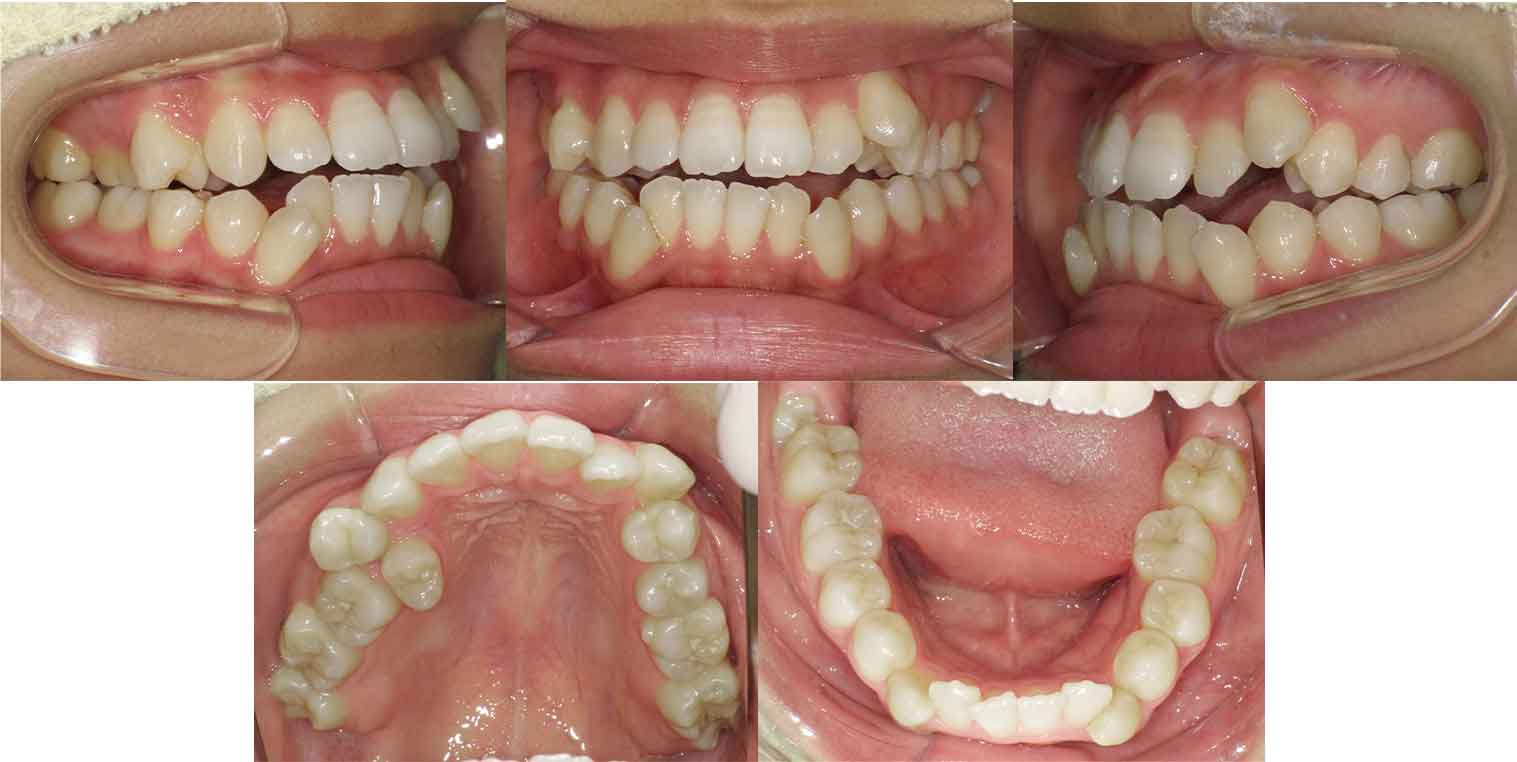

横浜市にお住まいの20代の女性の症例をご紹介。前歯のガタガタと開咬で悩まれている患者さんでした。上下左右の4番目の歯(第一小臼歯)を抜歯して舌側矯正(裏側矯正)でアンカースクリューと顎間ゴム(エラスティック)を併用して改善しました。

治療後

| 治療の方法 |

舌側矯正(裏側矯正)+アンカースクリュー |

| 治療期間 |

2年4か月 |

前歯の叢生(ガタガタ)と開咬を、舌側矯正(裏側矯正)で改善した20代女性の症例をご紹介。アンカースクリューやゴムかけを併用し、機能と見た目を両立した治療事例です。横浜まつざわ矯正歯科。